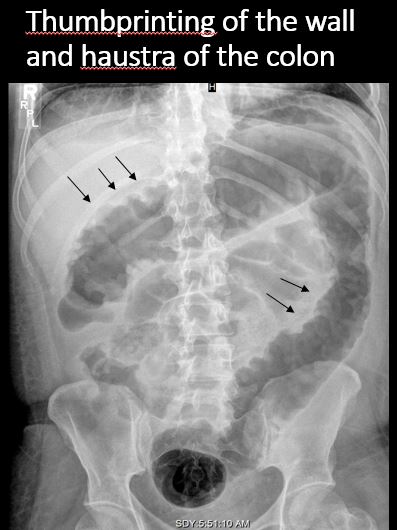

There is retroperitoneal air outlining the right psoas muscle likely from duodenal perforation, from recent endoscopy. There are a few distended loops of small bowel in the mid and lower abdomen.

Notify the clinical team verbally and immediately about retroperitoneal air likely indicating duodenal perforation from recent endoscopy.